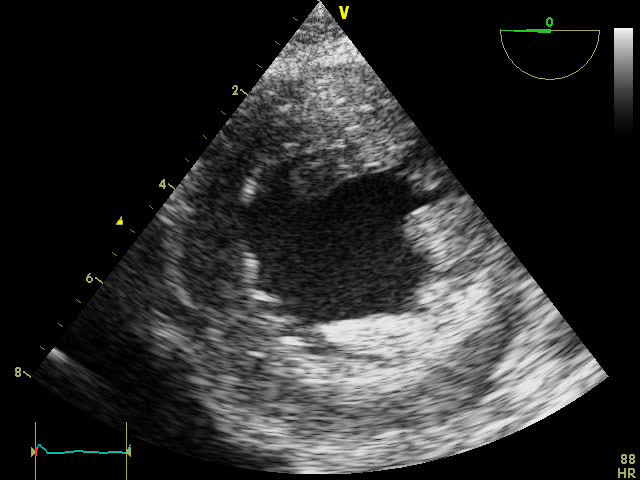

PSAX

TEE PSAX view of left ventricle with hypertrophy and hypovolemia: This transesophageal echocardiography (TEE) parasternal short-axis (PSAX) view shows a left ventricle with hypertrophy and signs of hypovolemia. The small diastolic volume, combined with the strong, effective contractions of the thickened heart muscle, highlights the heart’s effort to compensate for low blood volume. These findings are characteristic of hypovolemia in a hypertrophied left ventricle.